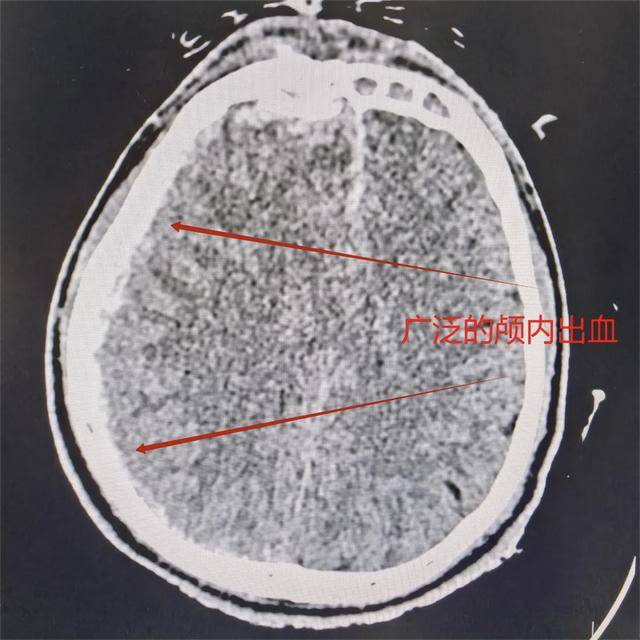

头部CT检查结果传来,伤情比预想中更为严峻,砂轮碎片面积不小,不仅穿透额骨,还深深嵌入脑内。颅内堆积的大量血肿已导致脑组织受压,中线明显偏移。额窦与鼻骨也出现粉碎性骨折。